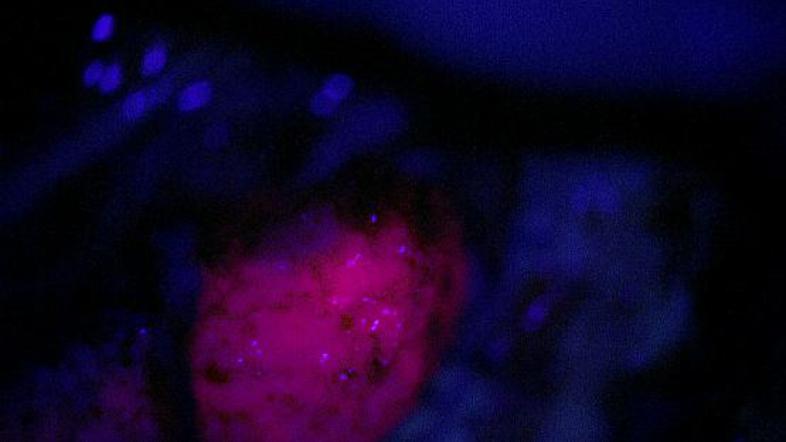

Tri ure pred operacijo pacient zaužije posebno 5-aminolevulinska kislino, ki se kot prašek raztopi v vodi. Tekočina se kopiči v tumorjih celicah možganov in se v njih presnovi v fotoodsevni presnovek, ki se pod osvetlitvijo z modro svetlobo začne svetlikati z značilno svetlo vijolično barvo (tumor) na temnomodrem ozadju, ki predstavlja  normalne možgane," pojasnjujejo na UKC.

Prvo operacijo sta sicer opravila nevrokirurga Tilen Žele in Alenka Vittori, 5-ALA pa jima je pomagala,  da sta pod mikroskopom in pod svetlobnim filtrom vidila tanke zaplate spremenjenih celic na obrobju tumorja, ki so na normalni svetlobi skoraj neločljive od normalnih  možganov, pod modro svetlobo pa se pokažejo v svetlo vijolični barvi, in se jih lahko tako vidno označene temeljiteje in varneje odstrani: